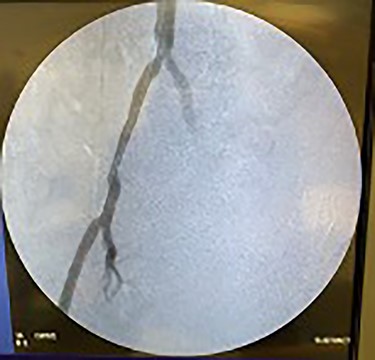

Catheter arteriogram results showed significant occlusion of the left iliac artery (Figs 3 and 4), the right iliac artery (Fig. 1), as well as the distal abdominal aorta (Fig. 2). There were numerous collateral vessels noted, indicating the presence of long-standing proximal stenosis (Fig. 1). The decision was made to use angioplasty to help widen the areas of stenosis. An 8 mm × 40 mm Passeo balloon was advanced from the right femoral artery into the left iliac artery (Fig. 7) and insufflated to 6 mmHg (Fig. 6). The balloon was allowed to remain expanded for 1 min and then was deflated. Next, the distal aorta was repaired in a similar fashion. The balloon was advanced into the distal aorta from the right femoral access and insufflated to 12 mmHg (Fig. 8). The balloon was allowed to remain expanded for 90 s.

Fluoroscopy of right iliac artery showing vast collateral vascular formation, indicating long-standing proximal obstruction.